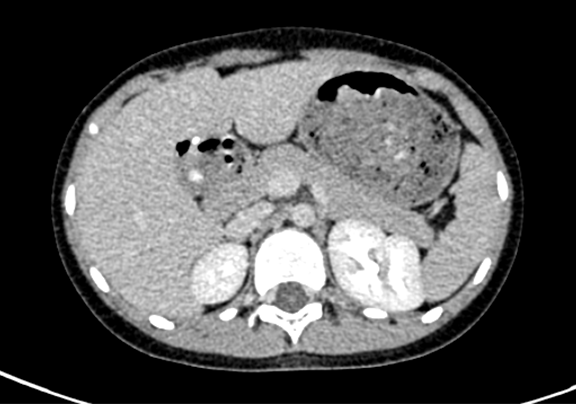

CT: 胆总管囊肿。

上腹部动态增强CT:符合先天性胆管扩张所见(I 型为主)。

术前CT检查:

动脉期

静脉期

平衡期